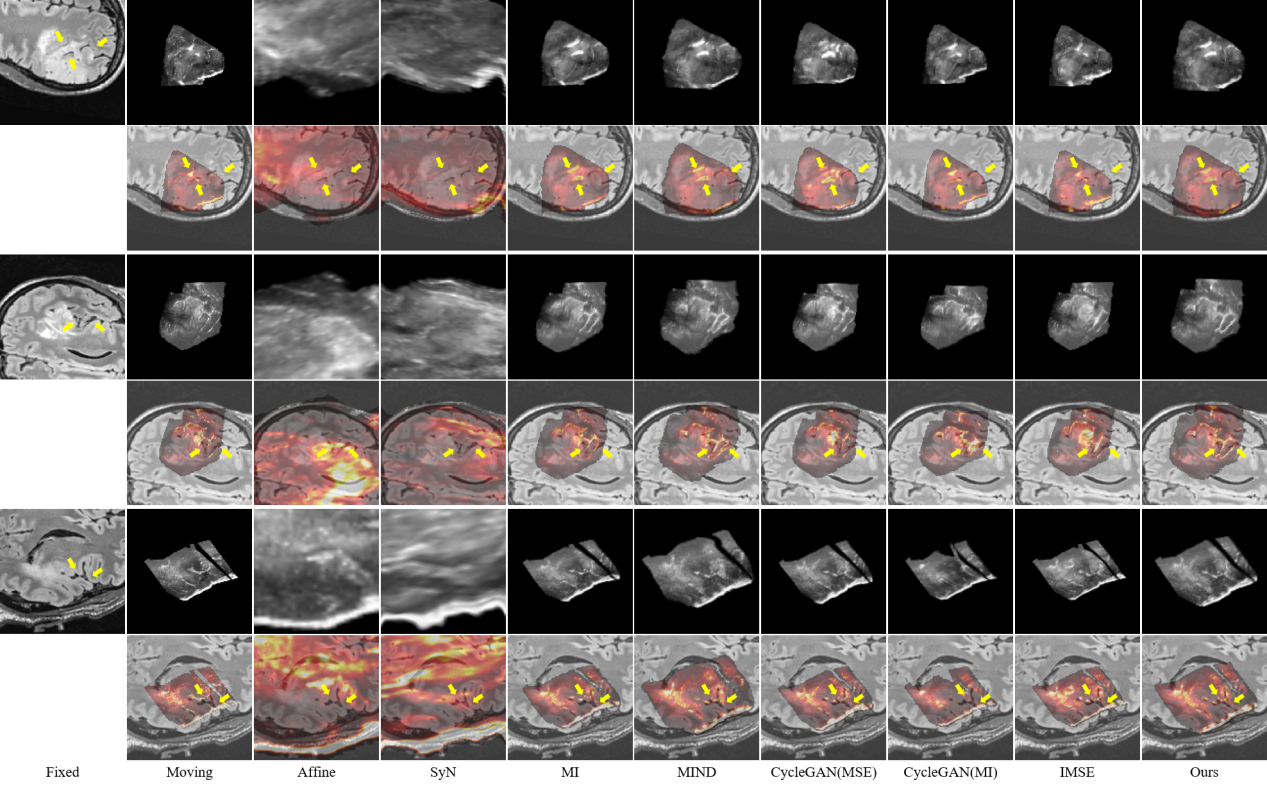

研究結(jié)果表明,SynMSE 在L2R 2022 CT-MR腹部數(shù)據(jù)集、臨床宮頸CT-MR數(shù)據(jù)集以及CuRIOUS MR-US腦數(shù)據(jù)集上均取得了最優(yōu)配準性能。與傳統(tǒng)方法相比,SynMSE顯著提升了Dice系數(shù)、降低了HD95與TRE誤差,實現(xiàn)了在復雜模態(tài)差異下的高精度解剖結(jié)構對齊。圖4-圖6分別為所提出方法在三個數(shù)據(jù)集上的定性結(jié)果展示,紅色標注代表固定圖像的目標器官區(qū)域,黃色標注代表浮動圖像與配準后圖像的目標器官區(qū)域。表示圖中結(jié)果顯示,SynMSE更好的克服了多模態(tài)圖像間的復雜分布差異,不僅實現(xiàn)了更精確的配準效果,而且有效保持了組織邊界與解剖拓撲的完整性,明顯優(yōu)于現(xiàn)有方法。

圖6:所提出方法與現(xiàn)有方法在CuRIOUS MR-US腦數(shù)據(jù)集上的定性效果(黃色箭頭指向圖像上的較為明顯的腦溝等顯著結(jié)構)